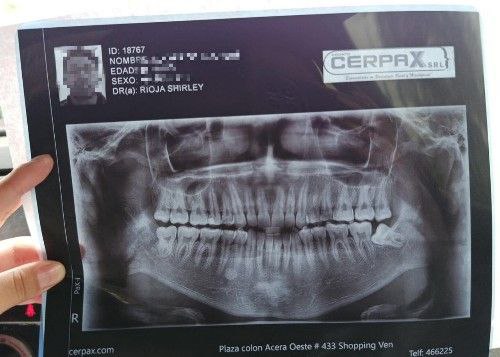

En el Centro Maxilofacial, brindamos atención de emergencia las 24 horas, los 7 días de la semana para el manejo de fracturas de mandíbula, utilizando tratamientos de vanguardia que permiten una rápida recuperación.

Aplicamos la técnica intrabucal de reducción de fractura sin cicatrices, logrando resultados funcionales y estéticos óptimos para nuestros pacientes.